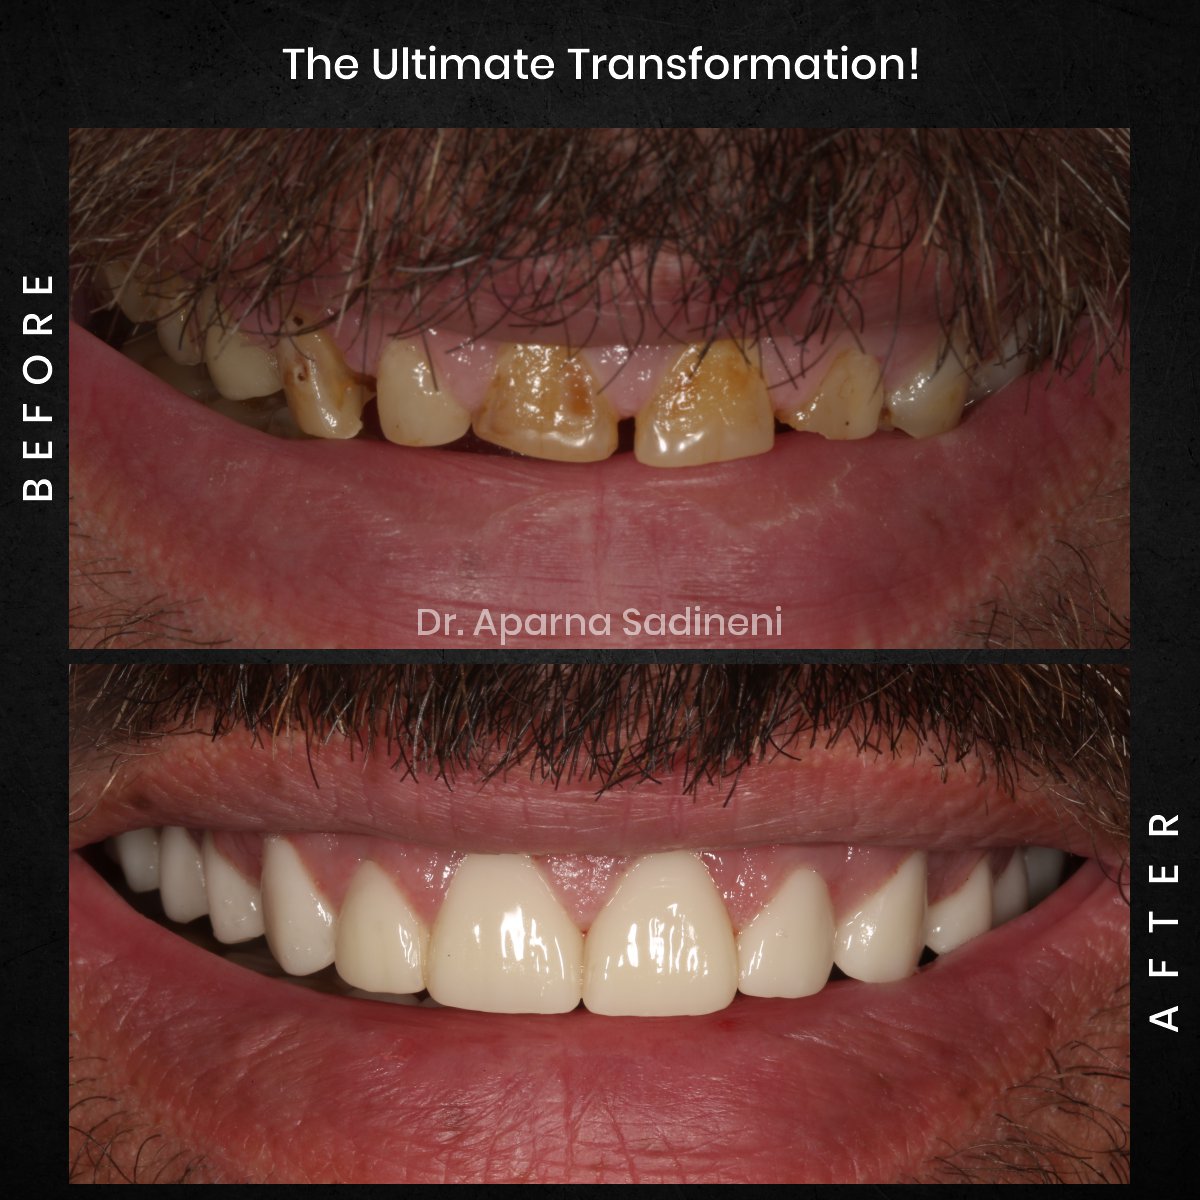

David's Smile